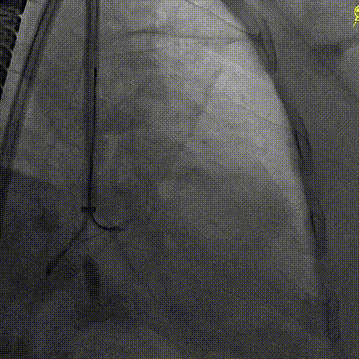

手术采用左侧股动脉入路与右侧股静脉入路,由股动脉入路将环形放置导管输送至瓣下预估深度并推送出合适角度,在高位开始多角度指引下导丝成环步骤。多学科团队紧密协作,在术前规划的DSA投射体位和科雨彤教授的超声引导配合下,宋光远教授精细操控,导丝顺利按预期路径环绕二尖瓣瓣叶,一次成型并将导丝头端送入升主,随后于升主中进行导丝抓捕,影像下对导丝环轨道进行充分验证,最后将导丝头端体外化,建立起固定环植入的重要轨道。

导丝围绕二尖瓣瓣叶成环

抓捕导丝并在超声下对导丝环位置进行验证